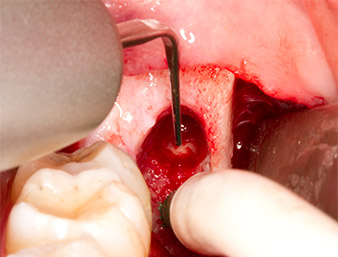

After block and local anaesthesia, the operating site was opened up and the soft tissue exposed for buccal retromolar access (Fig. 3).

sulcular incision

Fig. 3: The sulcular incision begins in mid-tooth 36 (LL6), with distal extension on the ascending ramus.

The tissue above the root remnant was not completely ossified and consisted for the most part of granulation tissue modified by inflammation (Fig. 4).